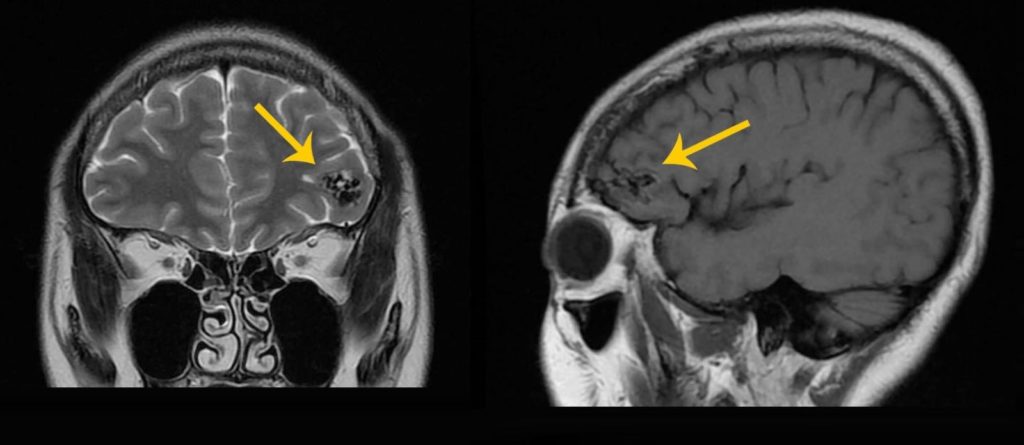

Magnetic Resonance Imaging (MRI) and Magnetic Resonance Angiography (MRA)

Magnetic Resonance Imaging (MRI) is a “radiation-free, non-invasive, painless” scanning imaging technique, which is very different from radio-induced X-Rays or Computed Tomography (CT scans). Besides of not requiring the injection of contrast agent, the advanced magnetic resonance machine can also achieve the effect of 3D three-dimensional brain angiography, and can accurately and clearly illuminate the location of cerebral arteriovenous malformation hemangioma and its relationship with normal brain tissue. In addition, MRI can scan different parts of the body to conduct a detailed screening of the whole body for patients without symptoms, and detect whether there is a hidden risk of stroke or cancer in the body structure.